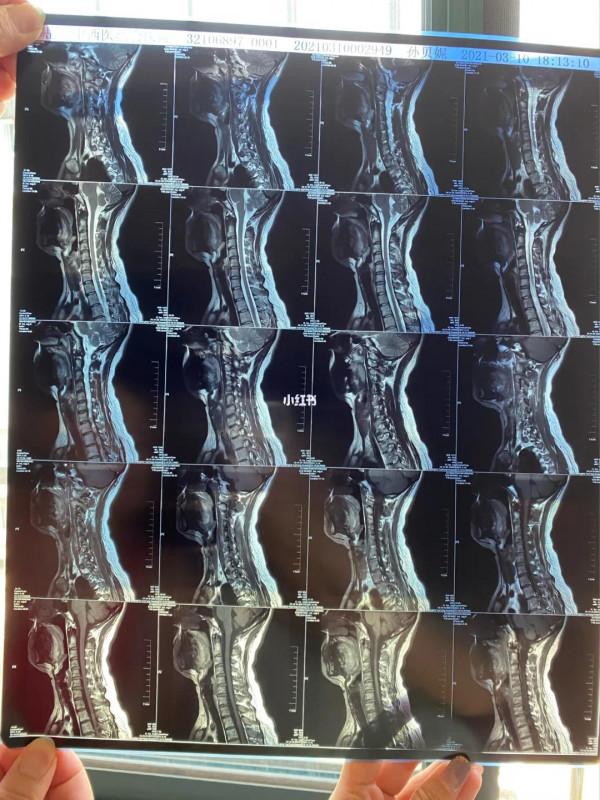

交感神經型頸椎病的典型症狀

交感神經型頸椎病的中醫治療